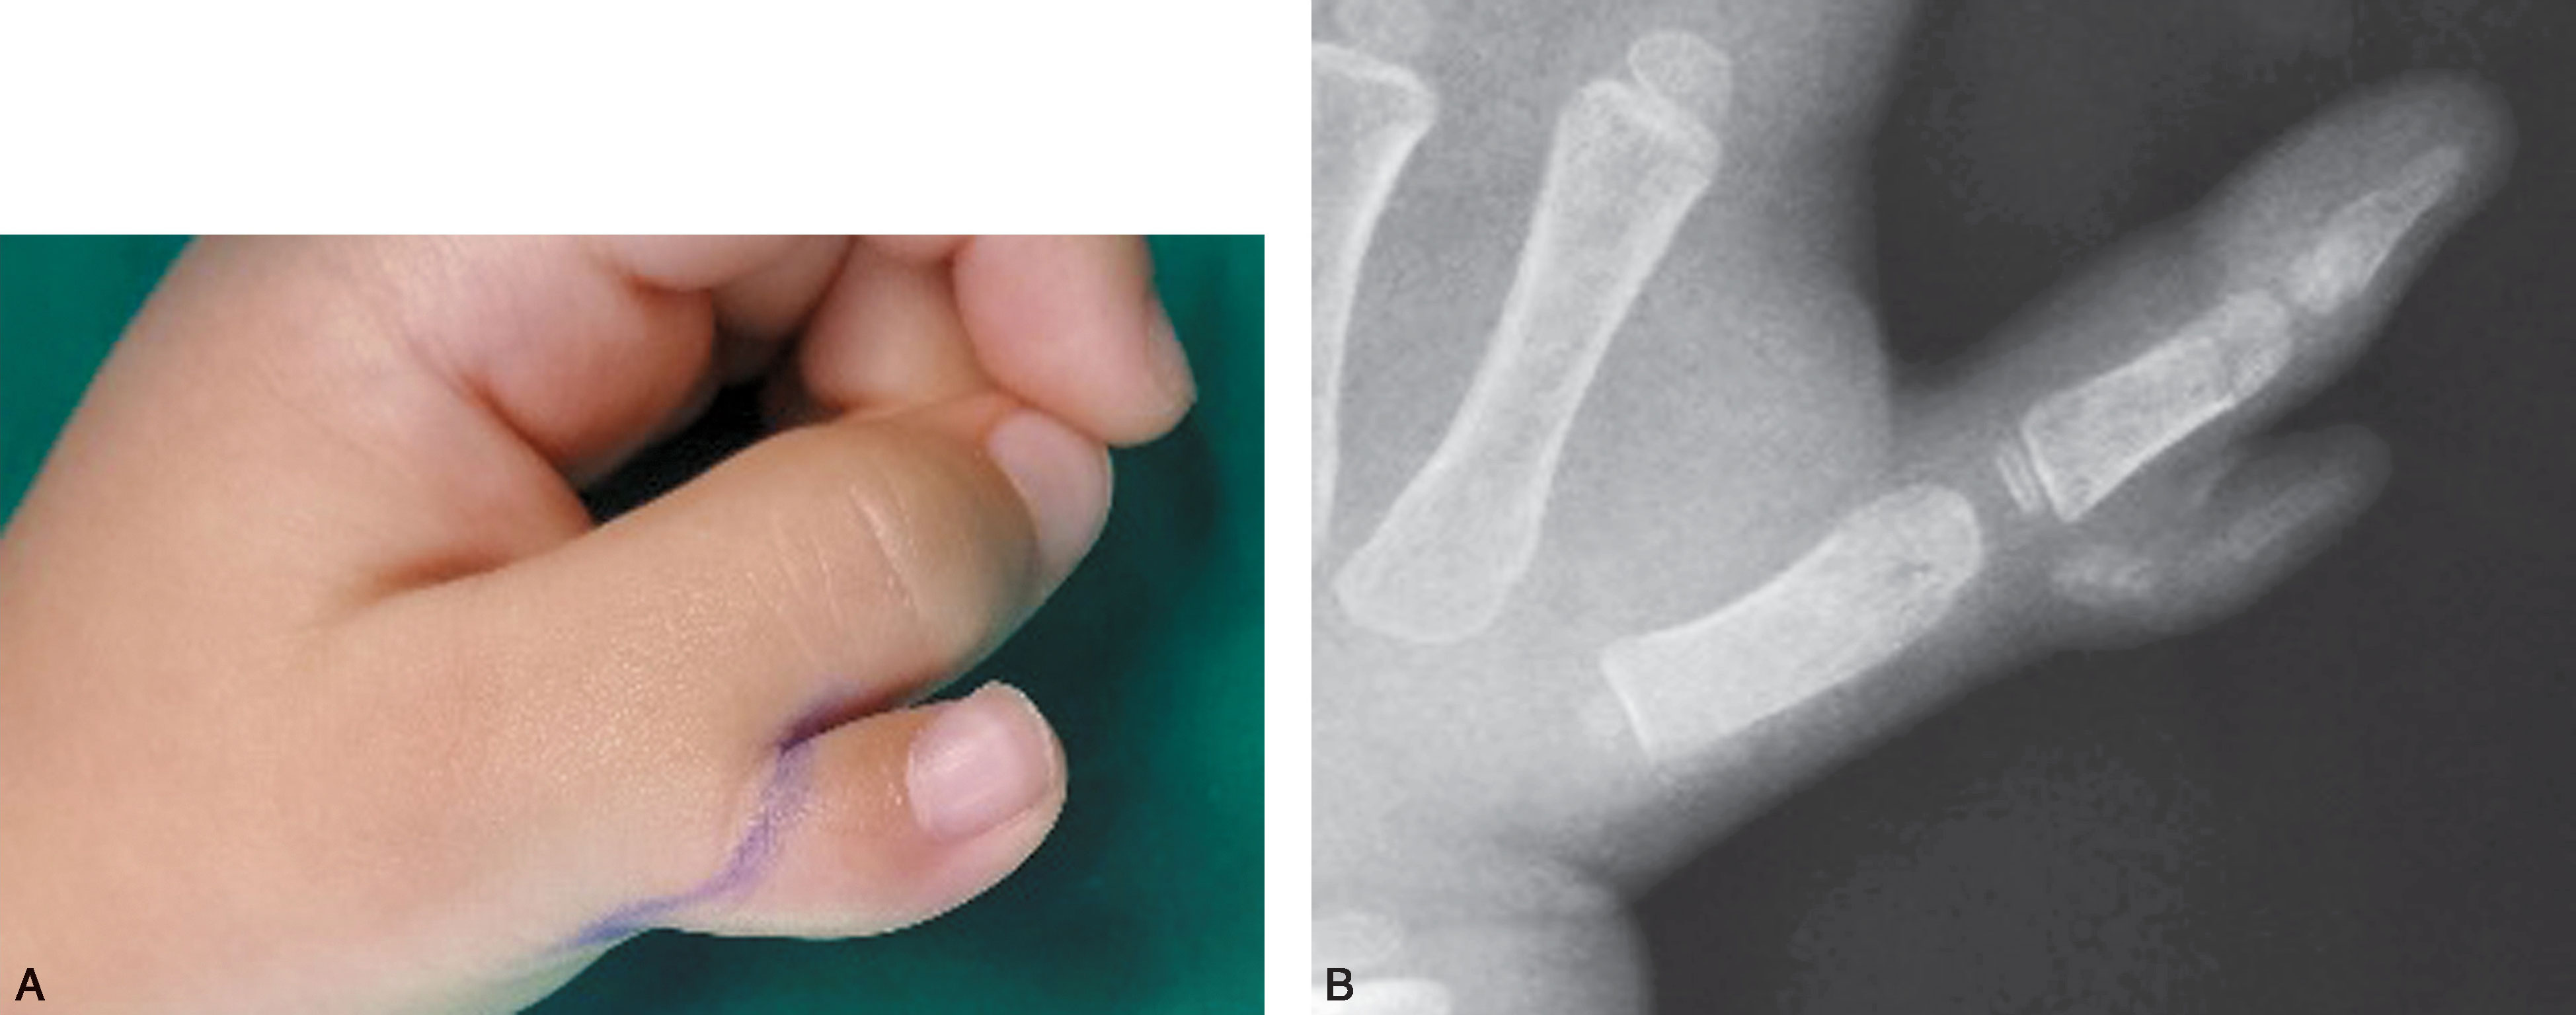

1.Ⅰ型 末节指骨未完全分裂,近节指骨正常或不正常,共用一个骨骺,并与近节指骨远端形成关节(图2-1-1~图2-1-4)。

图2-1-1 Ⅰ型病例1

A.主拇指与次拇指外形差异较大,各自有独立的指甲,远节尺偏(左侧);B.X 线片显示,虽然指骨远端分开,但基底共用一个骨骺,重建时需手术切除部分桡侧骨骺板,远节指骨尺偏需行近节指骨远端桡侧闭合楔形截骨,以纠正远节手指的尺偏畸形

图2-1-2 Ⅰ型病例2

A.主、次拇指外形差异较小,各自的指甲外形尚好且大小基本接近,融合在一起,可以选择切除任何一侧拇指,同时重建甲沟,或行主、次拇指融合;B.X 线片显示主次拇指远节指骨近端融合,远端分叉,分叉部分指骨大小差距较大,从X 线片结果看,可以切除桡侧拇指,也可行主、次拇指融合